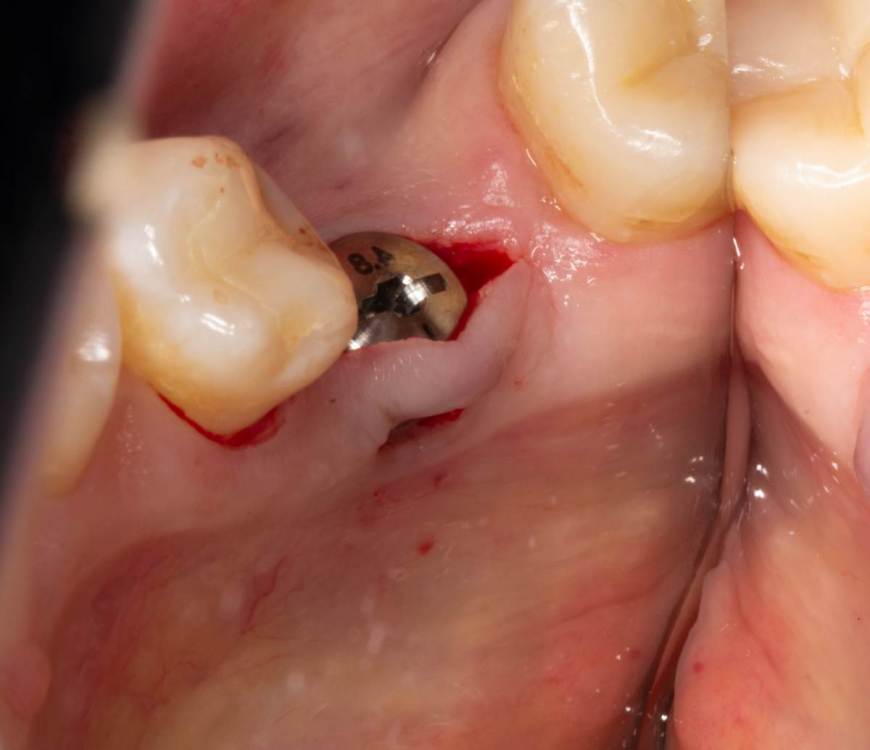

Женька Опубликовано 19 июня, 2023 Поделиться Опубликовано 19 июня, 2023 Здравствуйте, коллеги. Примерно с нового года начал ставить ТЛ имплантаты Дентиум. Что-то под заглушку (не поймал торки, представляете?). Что-то на низких формирвателях. И вот пришла пора протезирования, но отпустить к ортопеду не подготовив десну - не получается. Создал сам себе проблем, сегодня вот исправлял. Получилось неплохо? 3 Ссылка на комментарий

karasov Опубликовано 26 июня, 2023 Поделиться Опубликовано 26 июня, 2023 Я обычно не переживаю о торке в аналогичных условиях. Понимая, что имплантат прокручивается - беру заглушку(у ТЛ она относительно высокая обычно) или фдм и кручу от руки, старая создать при этом минимальный торк. Все таки имплантат хоть и не в притирку к стенкам ложа,но стенки эти есть, в отличие от ситуации когда вы ставите имплантат одновременно с синусом в 2 мм кости. И вы же не временную коронку прикручиваете, которая будет в процессе функционирования препятствовать интеграции имплантата 1 Ссылка на комментарий

Женька Опубликовано 26 июня, 2023 Автор Поделиться Опубликовано 26 июня, 2023 @karasov Так если он крутится уже на месте и болтается как карандаш. Хоть на заглушке, хоть на чём закручивай, не торкнет же уже Ссылка на комментарий

karasov Опубликовано 26 июня, 2023 Поделиться Опубликовано 26 июня, 2023 2 минуты назад, Женька сказал: @karasov Так если он крутится уже на месте и болтается как карандаш. Хоть на заглушке, хоть на чём закручивай, не торкнет же уже Для чего он должен торкнуть? Вы же его не нагружать собираетесь. Ссылка на комментарий

karasov Опубликовано 26 июня, 2023 Поделиться Опубликовано 26 июня, 2023 Что на ваш взгляд более предсказуемо интегрируется?: 1. имплантат с торком 60+ ,фиксированный в нативной кости 1/3 своей поверхности (апексом) и со временной коронкой, выведенной из прикуса , или 2. имплантат с ,,пересверленным,, на размер ложем, фдм вровень с десной и торком 0? Ссылка на комментарий

Женька Опубликовано 26 июня, 2023 Автор Поделиться Опубликовано 26 июня, 2023 @karasov конечно 2 вариант но как по мне любая супра- это уже нагрузка. Тот же пищевой комок может надавить хорошечно Ссылка на комментарий